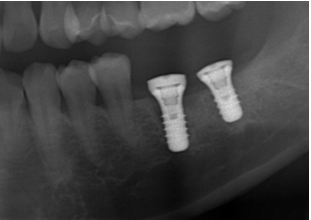

主訴:奥歯で噛めるようになりたい

After

症例情報

| 通院時の年齢 | 45歳 |

|---|---|

| 性別 | 女性 |

| 通院回数 | 6回程度 期間3ヶ月 |

| 通院目的 | 入れ歯を入れたくない |

| 処置内容 | インプラントを入れる治療 |

| 費用 | 85万(歯周病治療は保険治療) |

| デメリット・注意点 | 歯周病にかかっている患者さんは治療からインプラント治療に至るまでに1年近くかかる場合があります 治療後はれる可能性があります 虫歯の治療が並行して必要な場合があります |

| 備考 | 入れ歯による保険のかみ合わせの修復は引っ掛ける歯の寿命を短縮させ、せっかく治療したのにその引っかけの歯の歯茎がすぐに下がって虫歯になってしまう可能性や抜歯になってしまう可能性があります セラミックを使うインプラント上部の歯を使用することでインプラントの歯周病のリスクを下げることが出来ます |